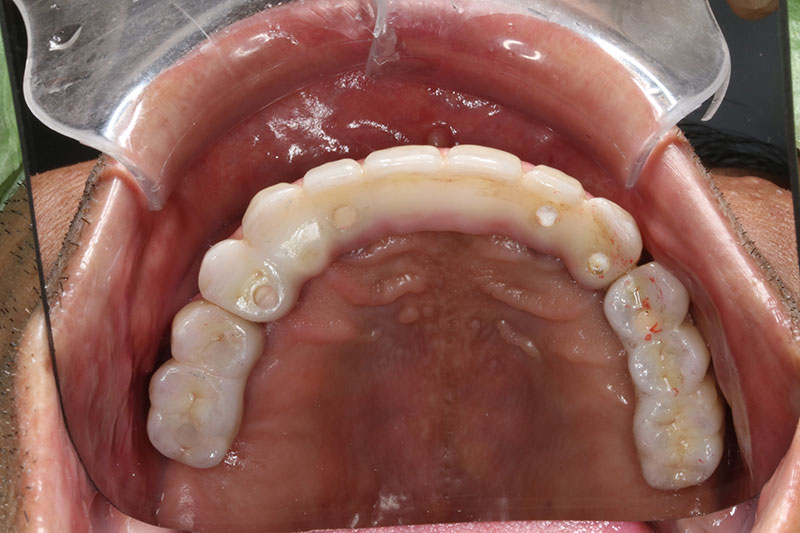

銀髮族植牙 全口植牙重建

案例一

術前

術後